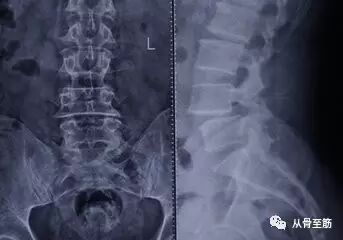

? ? 首先需要明确:大多数腰椎间盘突出症患者,医生根据临床症状或体征即可作出正确的诊断。在普通X光片上腰椎间盘无法显影,也就是说不能直接看到椎间盘的情况。只能看到椎间隙的变化,当有椎间盘突出时,大部分患者椎间隙会出现变窄。因此有经验的骨科医生可根据椎间隙改变,来分析是否有腰椎间盘突出。?

X光片虽不能作为确诊腰椎间盘突出症的依据,但可以排除某些疾患,如腰椎结核、腰椎肿瘤、脊柱滑脱、峡部裂、骶椎隐裂、腰椎骶化、骶椎腰化等。可以观察腰椎有无侧弯,腰前凸有无消失、椎体有无骨桥形成等。因为引起腰腿痛的原因有很多,所以需要通过X光片以初步排除这些情况。